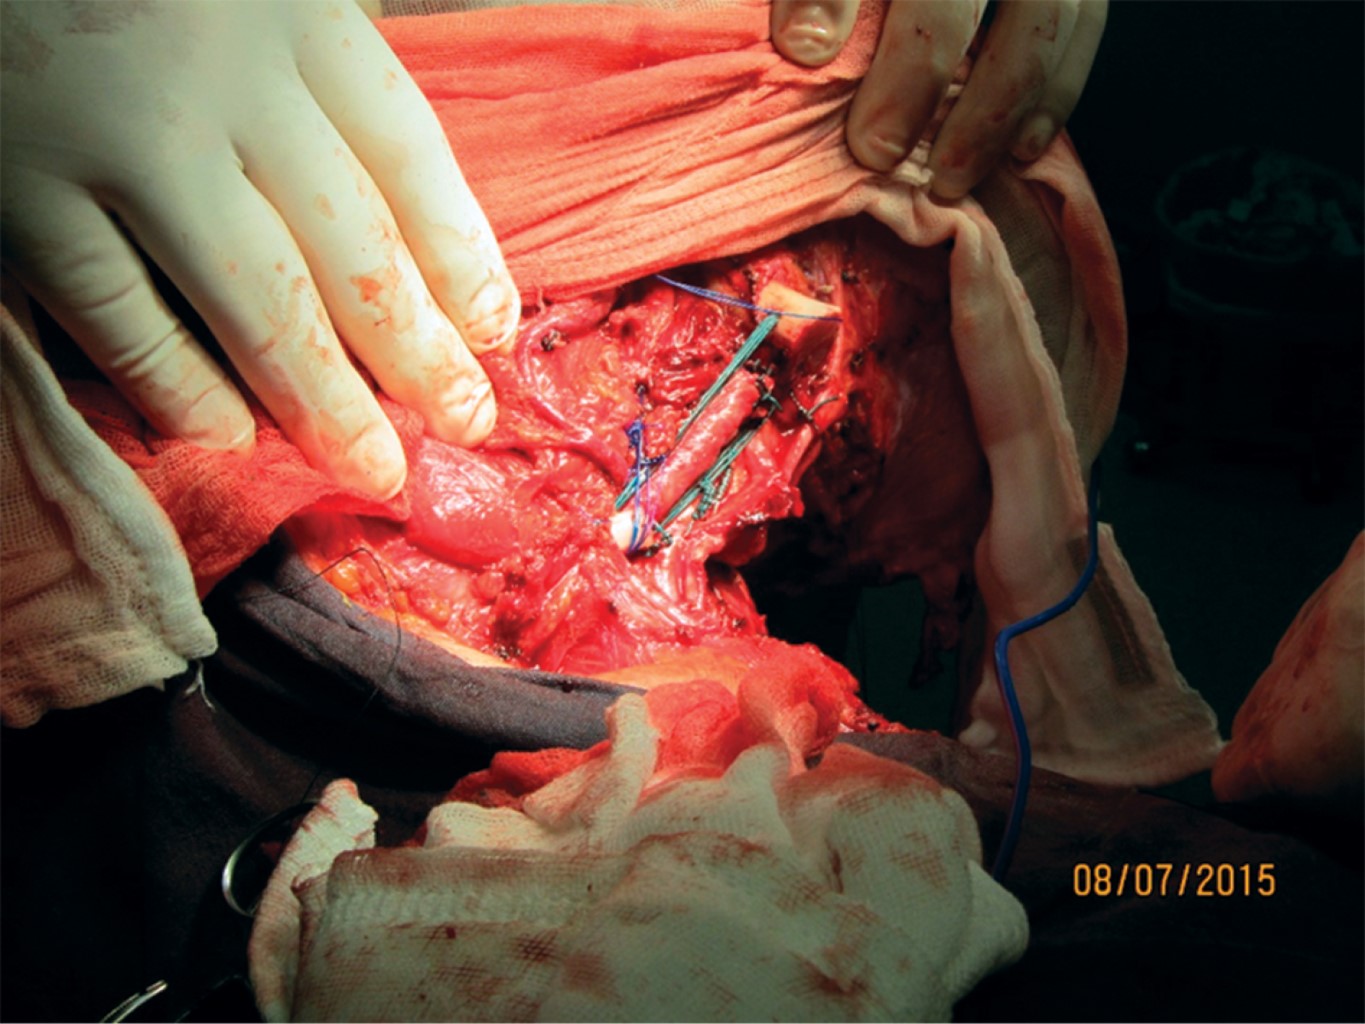

El 8 de julio de 2015 se lleva a cabo la cirugía de resección de cintura escapular derecha tipo 4, Tikhoff-Linberg sin uso de prótesis de escápula ni de húmero. Se administró cefalotina como antibiótico preoperatorio sin otro fármaco adicional, en el abordaje se realizó la incisión levantando un colgajo de piel supraclavicular, con disección de los músculos deltoides y supraescapulares; ya expuesta la zona (Figura 3) se realiza la disección de la masa con resección de la clavícula en sus dos tercios distales, así como eliminación del húmero proximal hasta su cuello quirúrgico. Se hizo anclaje del húmero a la clavícula con sutura de poliéster del número 3, se cerraron por planos las fascias aponeuróticas con vicryl del 2-0 con surgete anclado. No se presentó ni dehiscencia, ni seroma o hematomas en el postoperatorio, así como tampoco infección.

La incidencia del caso es 2-5:1'000,000, por lo que representa una rareza diagnóstica. En estudios donde se reporta el uso de la técnica de Tikhoff-Linberg tipo 410,11 se utilizan prótesis de escápula y/o húmero (Figura 7), en este caso se realizó una variable quirúrgica sin el uso de prótesis, por lo que se procedió a "anclar" el húmero de la clavícula residual por medio de sutura de poliéster (Figura 3), técnica de la que, a pesar de ser descrita por Linberg,8,11 no existen casos publicados sobre su uso. Se presenta radiografía posterior al procedimiento (Figura 8).